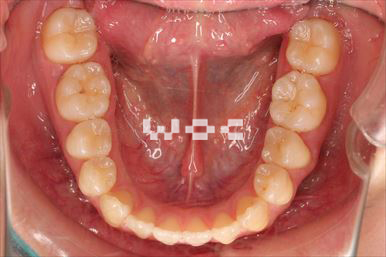

治療後1

治療後2

治療後3

治療後4

治療後5